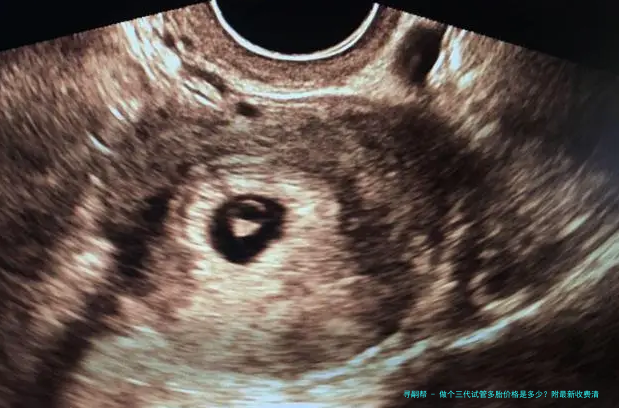

试管婴儿通过体外受精和胚胎移植的方式帮助不行自行受孕的夫妻完成生育心愿。这个技术慢慢形成为解决试管婴儿问题的有效手段。

三代试管婴儿是近年来发展起来的一项新技术,对比2代试管婴儿具有更高的成功率。它选用了新一代辅助生殖器械和先进的胚胎筛查技术,可以提高受孕率并减轻遗传病症风险。

三代试管多个胎儿指同一时间移植2个经由筛查后优异发育的胚胎,以增加成功率。